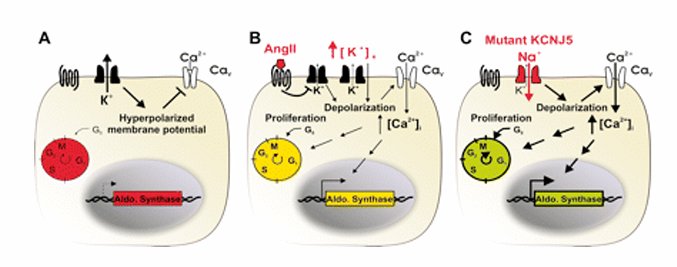

K-channel mutation in aldosterone producing adenomas